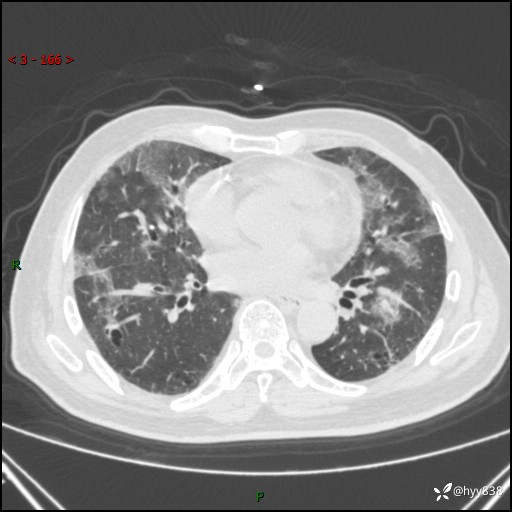

患者性别:男

患者年龄:64岁

简要病史:肝内胆管癌综合治疗后2周余,咳嗽、发热,咳白色泡沫痰。

辅助检查:CT

临床诊断:感染?

讨论:病变性质?